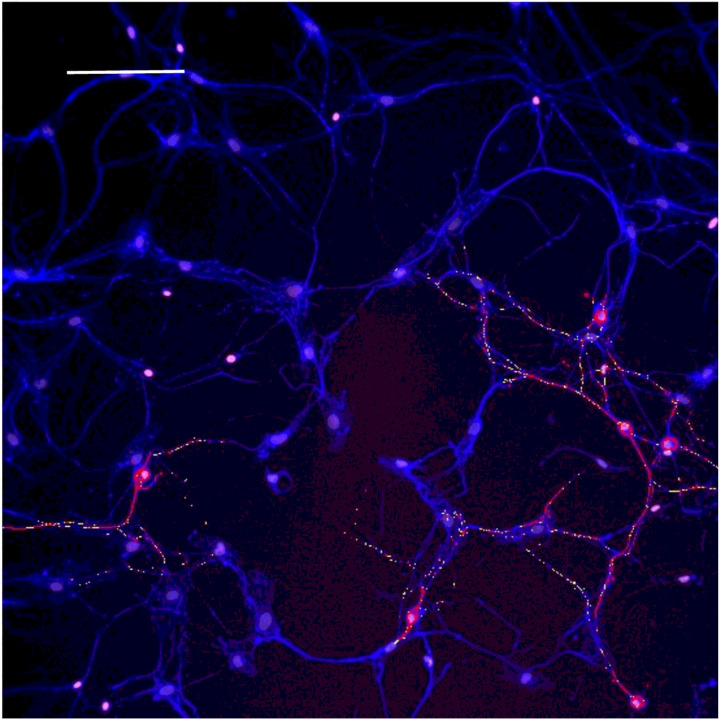

Based on concepts revealed from previous studies of KLS-13019-mediated inhibition of paclitaxel-induced inflammation (ref. Brenneman et al., 2022), the following inflammatory mediators were chosen to monitor effects of GPR55 siRNA: GPR55, NLRP3 and IL-1b. In the present study, the entire focus was on neuronal imaging as determined by beta-3 tubulin immunofluorescence. In Fig. 1, immunofluorescence spots of GPR55 and NLRP3 are shown indicating that these two measures of inflammation tracked together in the same location in GPR55-positive neurons. In all GPR55-positive neurons, NLRP3 immunoreactive (IR) spots were also observed. Most DRG neurons were not IR-positive for either marker, as only 25% of the neurons were positive for GPR55. Because an increase in NLRP3 was suggestive of an activation of the inflammasome − 3 complex, IL-1beta was also surveyed for IR spots in the DRG cultures. As shown in Fig. 2, the IR spot distribution in DRG neurons was compared for GPR55 and IL-1b. As in the observation made in Fig. 1, most neurons were not positive for either GPR55- or IL-1b. However, in all cases, neurons that were positive for GPR55 were also positive for IL-1b, although the distribution within the neurons was often slightly different, with IL-1b being more prevalent. To facilitate comparisons between the various analytes, changes were expressed as a percent of control. In Table 3, the control levels per neuron are presented for each analyte as determined by high content analysis of immunoreactive spots.